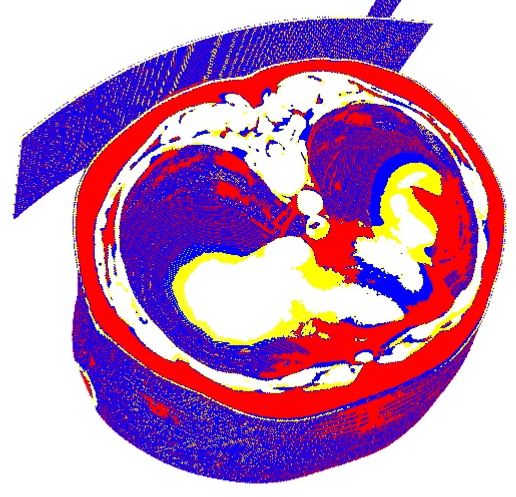

We have experimented with different values for the parameter: seemed to be too small as it could not separate a minimum of the required relevant features in the image, while starting with , the result image started to be too fragmented feature-wise. The 2D result for is presented in Figure 3.1. We also tried this algorithm in 3D on a CT volume for , as shown in Figure 3.2.

As it can be seen in the Figures 3.1 and 3.2, because the algorithm uses the pixels’ or voxel’s luminance levels to decide to which class each pixel belongs, and because multiple anatomical structures can have similar HU levels, this algorithm can not be used as such for the task of liver segmentation without any human intervention.